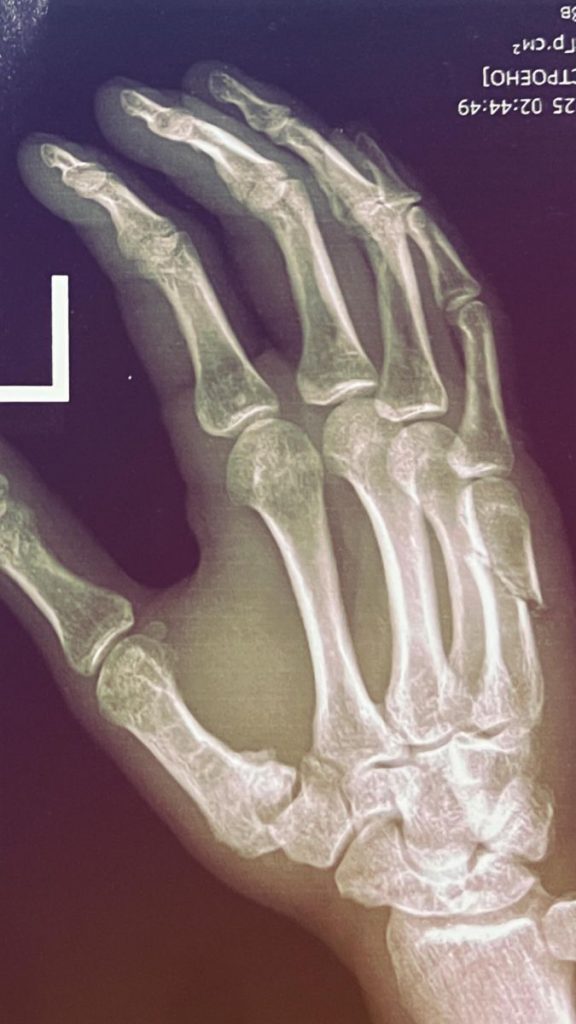

“To‘rt-besh kun oldin biroz noxushliklar bo‘lgandi. Hozir hammasi yaxshi, Xudoga shukur. Hol-ahvol so‘rayotganlarga katta rahmat. Jiddiy jarohat yo‘q. Tez orada ko‘rishamiz”, – deydi Mirzamatov.

Eslatib o’tamiz, uning 23-fevral kuni Olma-Otada tashkil etiladigan Octagon 70 turniri doirasidagi qozog‘istonlik Georgiy Kichiginga qarshi chempionlik jangi bekor qilingan.